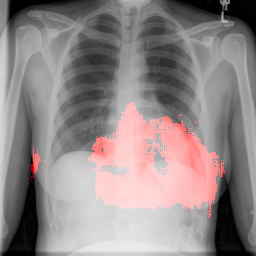

4.2.2 Pulmonary Edema Localization

In order to test the effectiveness of the localization procedure in areas other than the heart region, we chose pulmonary edema which occurs in the lung region. Also, pulmonary edema is detected by the net like white structure in the lung area. No anatomical shape change is associated with the abnormality. We have found that the localization is obtained best when the ROIs of lungs are taken to compute the map. Following the scheme in section 3.4, localization experiment on pulmonary edema is performed as shown in Fig. 8. It has been observed that the classifier is not sensitive to the fine features like septal or Kerley B lines. The localization is mainly obtained in the lung region where excess fluid is observed. Some localization regions are outside the lung region which occurs primarily for the fact that, even though the occlusion center is outside the lung, it occludes lung region and thus the probability drop occurs.

In a similar fashion, additional localization results for Pulmonary Edema is shown in Fig. 13. In Fig. 13(a) and (b) localization of two examples of CXRs with Pulmonary Edema is shown. As stated earlier the classifier localizes in the lung region. This is not the case when normal images are used to localize Pulmonary Edema as seen in Fig. 13(c) and (d). The localizations are obtained in random dense locations such as the sternum or heart. Like the cardiomegaly case, the histogram averages for CXRs with pulmonary Edema (Fig. 13(e)) shows a sensitivity toward pulmonary edema detection while the normal CXRs shows a spread out detection. It is interesting to note that, in the histogram of normal images high probability (¿0.85) is non-existent, thus ensuring low false positive rate. In the test set none of the normal images have been diagnosed as Pulmonary Edema. The failure cases are shown in Fig. 12. These CXRs are with Pulmonary Edema. However, the localization algorithm shows that one of them localizes in lungs whereas the other one shows a localization pattern similar to that obtained in normal CXRs.